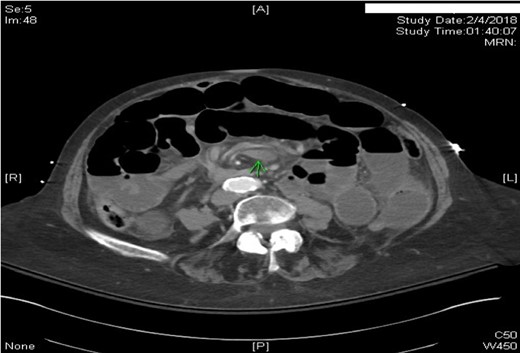

This case report presents an 80-year-old female with past medical history of Marfan syndrome with extensive cardiovascular manifestations including coarctation of the aorta, mechanical aortic valve and mitral valve replacement, heart failure with reduced ejection fraction (25–30%), and atrial fibrillation. The patient was admitted to the emergency general surgical service for complaints of acute onset colicky periumbilical abdominal pain, progressive abdominal distension, nausea and vomiting for 2 days. Emesis was described as non-bloody and non-bilious. Other pertinent history included one bowel movement 12 h prior to admission, which was non-bloody and inability to pass flatus for more than 24 h. No previous episode of abdominal pain of similar nature were elicitated. Physical examination was significant for mild abdominal distension and generalized tenderness to palpation in all quadrants without signs of peritonitis. Patient was afebrile and hemodynamically stable. Significant laboratory findings were INR of 2.20 (on warfarin for valve replacement), hyponatremia of 125, acute kidney injury with creatinine of 1.56. computed tomography (CT) of the abdomen/pelvis was significant for high-grade small bowel obstruction with a swirling of the superior mesenteric artery (SMA) and superior mesenteric vein (SMV) suggesting rotation of intestinal mesentery (Fig. 1) [5]. The SMV was located to the right of SMA, a reliable finding against intestinal malrotation [5] (Fig. 2). Further, there was no radiologic evidence of malrotation like transposition of SMA and SMV, the horizontal part of the duodenum not reaching medioventral line, and malposition of ileocecal junction [5]. The INR was not reversed with FFP and Vitamin K due to concern for stroke. Emergent exploratory laparotomy within 6 h of admission was performed which was significant for midgut volvulus with the small bowel rotating around the base of mesentery a complete 360°. There were no signs of ischemia, and hence manual untwisting of the bowel was performed [2, 5]. The cecum was noted to be on the right lower quadrant and ligament of Treitz was on the left upper quadrant. The small bowel mesentery was noted to appear long with narrow base and floppy likely contributing to hypermobility of the small bowel. The patients postoperative course was uneventful, and she was discharged to skilled nursing facility for further rehabilitation.

Axial CT scan of Abdomen with IV contrast: Swirling of the superior mesenteric artery and superior mesenteric vein. Proximal and mid small bowel dilatation with differential air–fluid level.